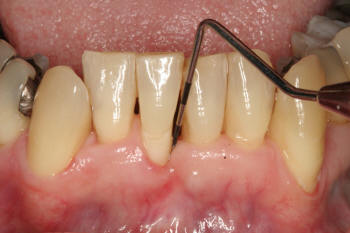

Retracción

gingival |

Realizar el

sondaje periodontal para identificar bolsas

sangrantes |